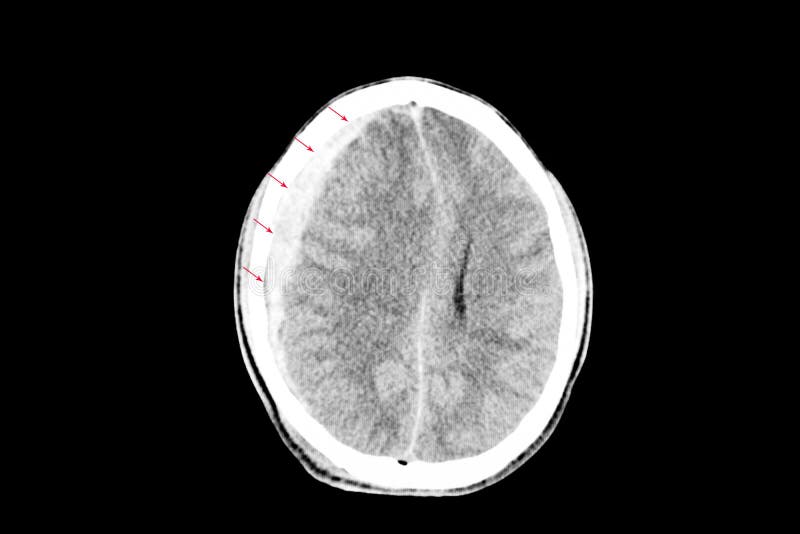

Testa Di Scansione Tc Con L Ematoma Subdurale Atrofia Foto Stock Alamy

Scansione Tc Del Cervello Che Mostra L Ematoma Subdurale Foto Stock Alamy

Scansione Tc Della Testa Di Un 77 Anno Vecchio Che Mostra Un Acuto L Ematoma Subdurale Foto Stock Alamy

Scansione Tc Della Testa Che Mostra Un L Ematoma Subdurale Foto Stock Alamy

Scansione Tc Della Testa Con L Ematoma Subdurale Foto Stock Alamy